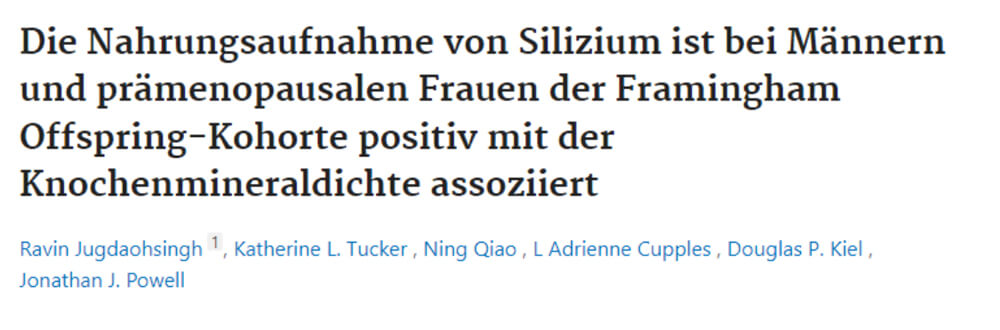

Je kraakbeen kan alleen regenereren als het de juiste bouwstenen krijgt. Silicium uit bamboe-extract levert deze essentiële stoffen en activeert de lichaamseigen kraakbeenproductie.

Maar alleen als de ontsteking wordt gestopt en de barrières worden verbroken, kan het kraakbeen worden herbouwd. Dit is de sleutel op lange termijn tot gezonde, veerkrachtige gewrichten.

Kraakbeen opnieuw opbouwen: Silicium ondersteunt de regeneratie en zorgt ervoor dat je gewrichten op de lange termijn veerkrachtig blijven.